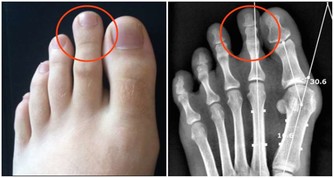

傳統醫學認為桑椹味酸,性微寒,具有提高人體免疫力、補血滋陰、生津止渴、潤腸燥等功效,主治陰血不足而致的頭暈目眩、耳鳴心悸、煩躁失眠、腰膝酸軟、鬚髮早白、消渴口乾、大便乾結、滋陰補血、明目安神、利關節、去風濕、解酒等功效,在《中國大藥典》、《本草拾遺》、《滇南本草》、《唐本草》等醫學典籍中均記載有桑果的防病保健功能。